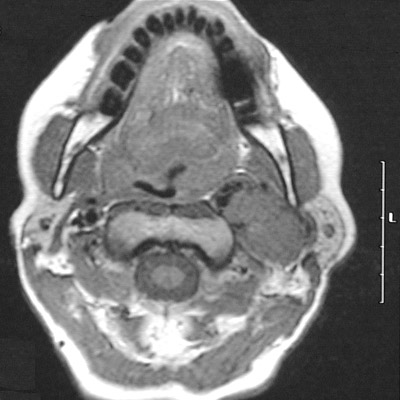

| The axial MRI scan above, a T1 weighted post-gadolinium view demonstrates a paraganglioma enhancing with the contrast. The mass does not enhance in the T2 weighted FSE axial view below. Paragangliomas arising in the carotid body rarely secrete significant amounts of catecholamines, unlike the "extra-adrenal pheochromocytomas" arising in paraganglia of the retroperitoneum. |